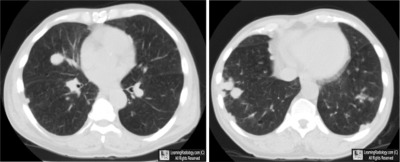

Additional Images - Axial CT images of the chest

Axial CT images of the chest

4. Rheumatoid Nodules

Rheumatoid Nodules

- Rare

- Immune-mediated granulomas frequently with necrotic centers

- They are almost always associated with long, standing active rheumatoid arthritis

- More frequent in males with high titers for rheumatoid factor

- Also more frequent in smokers and those who already have subcutaneous nodules